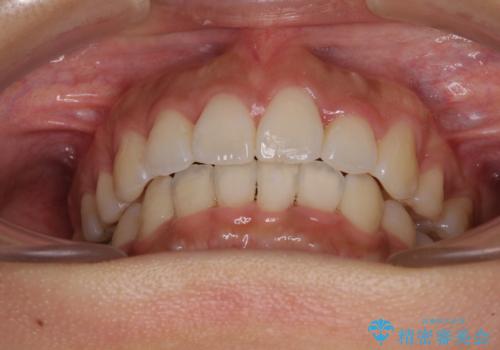

下顎の正中を上顎に合わせる処置が難航し、期間が長引きました。

最終的には上下の正中も合い、横顔の印象が変わるほどスッキリとした口元となりました。